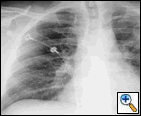

The patient was hemodynamically stable and his physical examination was unremarkable. His laboratory examination did not reveal any electrolyte abnormalities or anemia. An admission chest roentgenogram was obtained and revealed a LUL abnormality (Figure 1). Consequently, a computed tomogram (CT) was obtained and confirmed the LUL abnormality as a thick-walled 2 cm LUL cavity and also revealed the presence of a contrast enhanced, 7 mm mural, soft tissue nodule with the cavity (Figure 2). A high-resolution CT with three dimensional reconstruction demonstrated communication from the LUL nodule to vessels adjacent to the cavity wall (Figure 3).